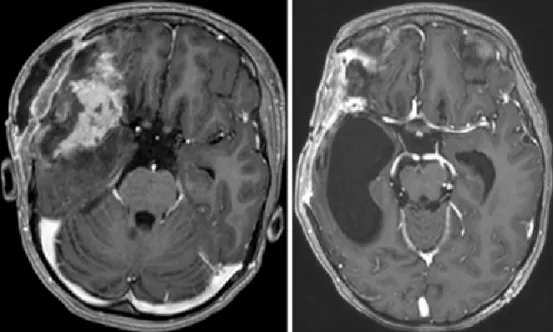

图4.左图:开颅术后第1天获取的轴位T1加权钆增强MR图像,显示肿瘤次全切除术后改变及周围脑软化。

右图:开颅术后3个月获取的轴位T1加权钆增强MR图像,显示侧裂远端有残留肿瘤,并可见右侧颞角扩张。因脑积水已行脑室腹腔分流术。